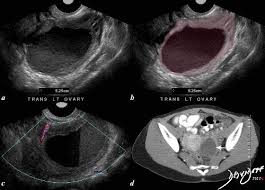

Ct scans and the diagnosis of endometriosis ct scans can be used to visualize endometriosis in some areas of the abdomen, but are not very efficient in visualizing the pelvic organs, such as the uterus. Reproductive medicine associates of connecticut with fertility clinics in connecticut and new york. Ct hrct is the modality of choice for thoracic endometriosis, which may demonstrate presence of pneumothorax, hemothorax or nodules which may change in nature cyclically. Detection and localization of deep endometriosis by means of mri and correlation with the enzian score. Moreover, the appearance of implants and endometriomas is.

The Radiology Assistant Endometriosis Mri Detection from radiologyassistant.nl B, ct scan shows a nonspecific mass involving the right rectus muscle (arrow) subsequently proven to be endometriosis. After taking your medical and symptom history, and after performing a pelvic exam, your provider may recommend imaging. A ct or mri may show the endometriosis. Unusual sites of implantation and associated complications may make. Ct, endometriosis, female pelvis, mri, ultrasound. Endometriosis is a painful condition in which tissue that normally lines your uterus (endometrial tissue) grows in other parts of your pelvis, such as your ovaries or fallopian tubes. It can get worse before and during your period. An ultrasound, a ct scan, or an mri can make detailed pictures of your organs.

The new york endometriosis center which is one of the leading endometriosis treatment and gynecologic surgery centes in the world with offices in new york and greenwich. The ct and mr characteristics of abdominal wall endometriosis are nonspecific, both showing a solid enhancing mass in the abdominal wall. The most common sign of endometriosis is pain in your lower belly that doesn't go away. Endometriosis happens when the endometrium, tissue that usually lines the inside of your uterus, grows outside it. The most common symptom is pelvic pain. Endometriosis is a condition in which the inner lining of the uterus (endometrium) grows outside the uterus in locations such as the fallopian tubes, ovaries, bladder, or. Ct scans and the diagnosis of endometriosis ct scans can be used to visualize endometriosis in some areas of the abdomen, but are not very efficient in visualizing the pelvic organs, such as the uterus. The use of ultrasounds, magnetic resonance imaging (mri), computerized tomography (ct scan), and certain endometrial biopsy samples may be used as part of a diagnostic workup, but to date, anything less than surgical confirmation of endometriosis is considered uncertain. Tell the healthcare provider if you have ever had an allergic reaction to contrast liquid. It is a painful chronic disease that is estimated to affect 10% of women of all ages and backgrounds during their reproductive years. There are also no specific blood tests to diagnose endometriosis. Imaging exams, such as ultrasound, mri, or ct scans are used to take pictures of the inside of your body. An ultrasound, a ct scan, or an mri can make detailed pictures of your organs.